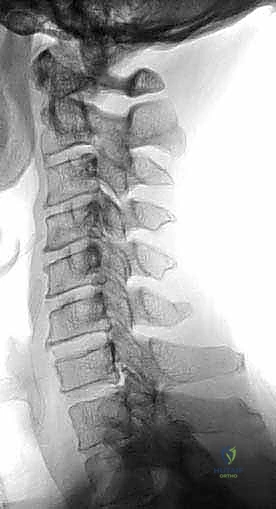

- الأشعة السينية الديناميكية (X-Rays): لتقييم استقرار العمود الفقري أثناء ثني ومد الرقبة.

يتكون العمود الفقري العنقي من سبع فقرات (C1 إلى C7)، تفصل بينها أقراص غضروفية تعمل كممتص للصدمات وتسمح بحركة الرقبة بمرونة. يمر الحبل الشوكي – وهو حزمة الأعصاب الرئيسية التي تنقل الإشارات بين الدماغ وبقية الجسم – عبر قناة عظمية ضيقة داخل هذه الفقرات.

يحدث "تضيق النخاع الشوكي" عندما تضيق هذه القناة العظمية، مما يؤدي إلى خنق الحبل الشوكي. قد يحدث هذا التضيق في مستوى واحد (بين فقرتين) أو يمتد ليشمل عدة مستويات، مما يتطلب إزالة جسم الفقرة بالكامل لتحرير الضغط.